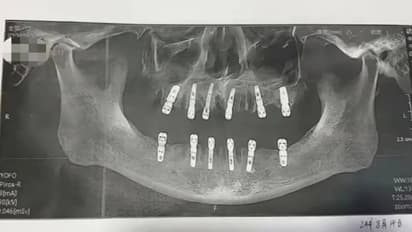

ഹുവാങ് ഒപ്പിട്ട സമ്മതപത്രം അനുസരിച്ച്, ഒരൊറ്റ ദിവസം തന്നെയാണ് ഇദ്ദേഹത്തിൻറെ 23 പല്ലുകൾ പറിക്കുകയും പുതിയതായി 12 പല്ലുകൾ വെച്ച് നൽകുകയും ചെയ്തത്. യുവാൻ എന്ന ശസ്ത്രക്രിയാ വിദഗ്ധൻ ആണ് തൻറെ പിതാവിൻറെ ശസ്ത്രക്രിയയ്ക്ക് നേതൃത്വം നൽകിയത് എന്നാണ് ഷൂ പറയുന്നത്. ചികിത്സയ്ക്ക് ശേഷം, ഹുവാങിന് അതികഠിനമായ വേദന അനുഭവപ്പെട്ടിരുന്നു. ഒടുവിൽ ആഗസ്റ്റ് 28 ന് ഹൃദയസ്തംഭനം ഉണ്ടായതോടെ അദ്ദേഹം മരണപ്പെടുകയായിരുന്നു.